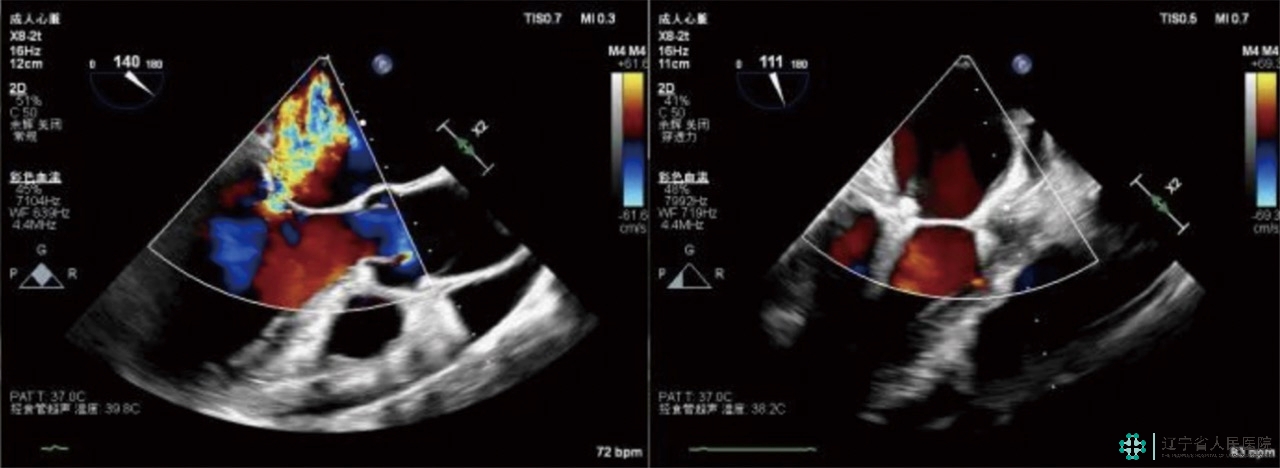

图说:术前术后心脏超声对比

二尖瓣钳夹术需要栾波主任带领的临床结构性心脏病团队、丁明岩副主任带领的心脏超声团队、张静主任带领的麻醉科团队多学科密切配合,在全麻状态下经股静脉置管、经食道超声(TEE)引导房间隔穿刺后置入导引鞘管,将夹合器精准送达二尖瓣反流区,在TEEX线引导下,手术团队利用二尖瓣夹(Mitraclip)准确捕获二尖瓣叶,试夹闭后超声证实有效,释放成型夹,术后超声评估夹闭区域内测反流几乎消失、夹合稳定、肺静脉逆流改善、平均跨瓣压差3mmHg,瓣口面积2平方厘米,患者各项生理指标正常,最终高质量地为患者完成了MitraClip,术后二尖瓣关闭不全程度由极重度变为轻度,手术顺利完成,大大改善了患者的心功能。